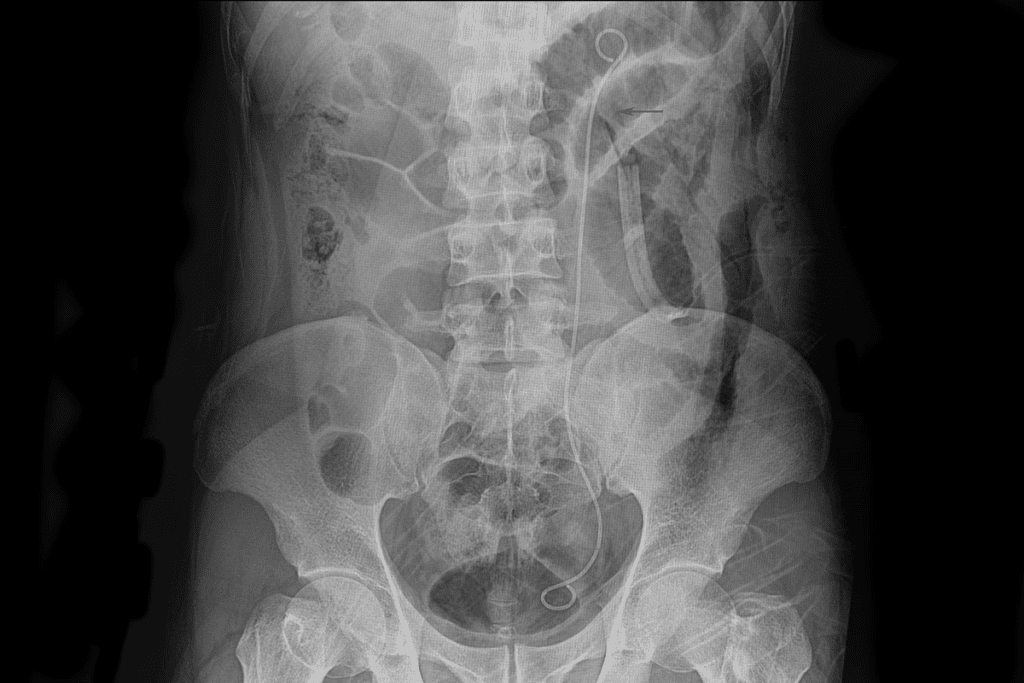

Doctors use imaging tests and other exams to find the blockage. They might use ultrasound, CT scans, or intravenous pyelography (IVP). These help see the urinary tract and find any blockages.

Other patients, like those with ureteral obstruction from kidney stones, might get pain management and hydration. In some cases, ureteral stenting is needed to keep the ureter open.